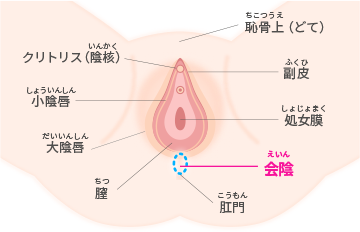

会陰切開について東京・世田谷での出産・分娩なら国立成育医療研究センター 産科。

会陰切開 をするタイミングは?痛みはある?切らない人もいる?会陰切開の不安と疑問に産婦人科医がお答えBaby-mo ベビモ。

会陰切開、吸引・鉗子分娩 出産のときの大切な医療処置たまひよ。

会陰切開 をするタイミングは?痛みはある?切らない人もいる?会陰切開の不安と疑問に産婦人科医がお答えBaby-mo ベビモ。

会陰切開、吸引・鉗子分娩 出産のときの大切な医療処置たまひよ。

会陰部贅皮切除術銀座の美容外科・皮膚科ならルーチェクリニック。

会陰部、肛門のたるみの治療東京・銀座で産後、便秘による皮膚の傷跡、コンプレックスでお悩みならルクスクリニック。